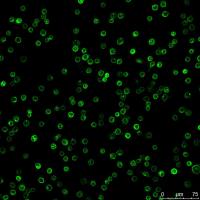

细胞库 / 细胞培养、技术服务